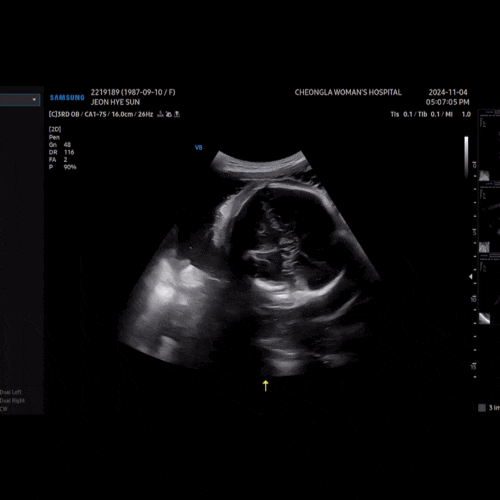

임신 33주 증상 입원 진료

임신 33주 그녀의 휘날리는 머릿결 안녕하세요 남매둥이 임신 중인 쩐여사예요. 어제 임신 33주 차 진료를 ...